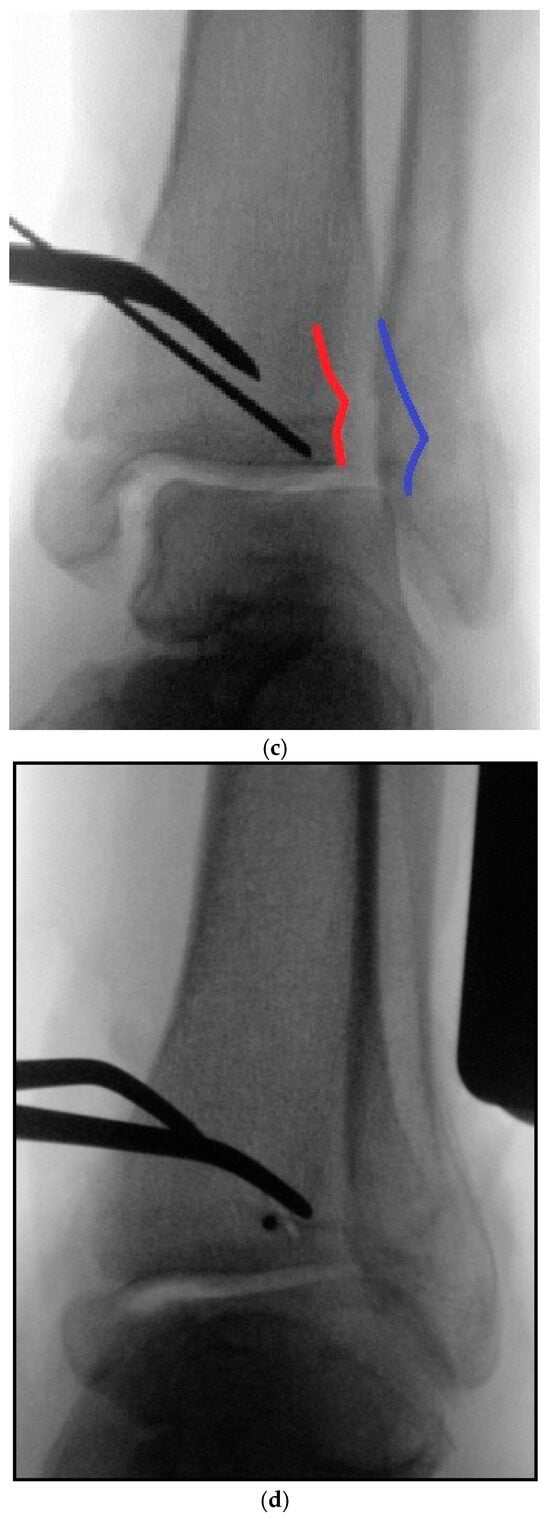

5.2. Inside-Out Fixation of the Posterior Malleolus Using a Headless Double-Threaded Compression Screw

5.4. Medial Malleolar Cancellous Screw Fixation Using the Modified Posteromedial Approach

5.5. Reamed Intramedullary Locking Nail Fixation of the Distal Fibular Fracture